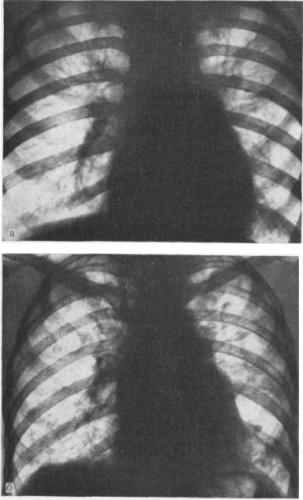

Рентгенологическая картина полиморфная, потому что показывает проявления не только самого пневмосклероза, но и сопутствующих болезней: эмфиземы легких, бронхоэктатической болезни, бронхита с хроническим течением и проч. Типичные петлистость, усиления и деформация легочного рисунка по ходу бронхиальных разветвлений, поскольку уплотняются бронхиальные стенки, имеют место склероз и инфильтрация перибронхиальной ткани.

Над пораженной зоной физикальные обследования обнаруживают ослабление дыхания, сухие или влажные хрипы, притупление перкуторного звука. Достоверным диагностическим методом является и исследование легких. Даже если симптомов нет, рентген помогает обнаружить изменения при их наличии, характер их, распространенность, то, насколько они выражены. Более точно оценить состояние нездоровых зон ткани легких могут магнитно-резонансная томография, бронхография, КТ легких.

Рентгенограмма показывает такие изменения пораженного легкого:

- уменьшение его в размерах

- усиление легочного рисунка по ходу разветвлений бронхов

- легочный рисунок сетчатый и петлистый по причине деформации стенок бронхов

- «сотовое легкое» в нижних отделах

Флюорография при пневмосклерозе

При любых жалобах на кашель и любую дыхательную симптоматику, нужно пройти обязательно флюорографическое обследование органов грудной клетки. Каждый год в целях профилактики и раннего выявления пневмосклероза, туберкулеза и прочих подобных заболеваний все лица от 14 лет должны проходить медицинский осмотр. При пневмосклерозе снижается жизненная емкость легких, низкий индекс Тиффно (который является показателем проходимости бронхов).